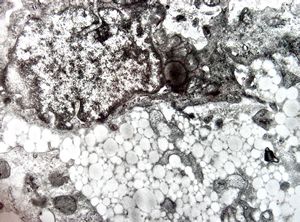

M,54y. | duodenum … Whipple disease, foamy histiocyte

lipid malabsorption

jejunum … lipid malabsorption